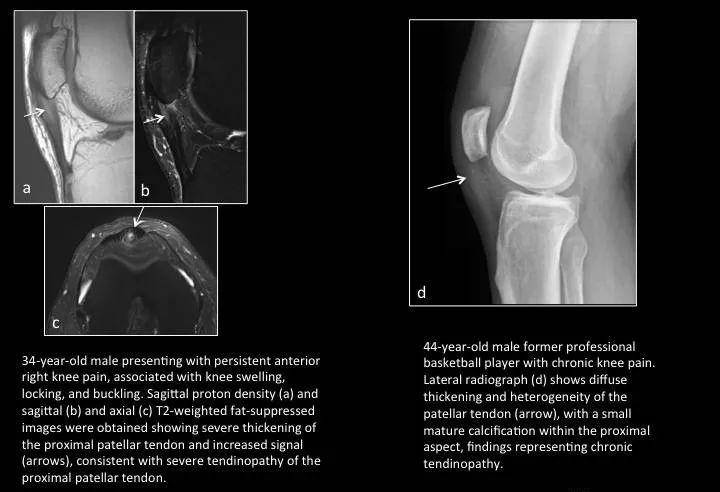

Fig. 19: Patellar tendinopathy

图19:髌腱末端病(髌腱腱病)